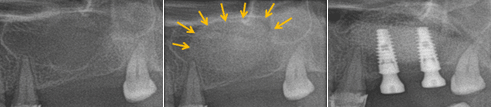

상한 앞니를 발거하고 즉시 임플란트를 식립하여 회복한 증례 - 상악동 거상술을 통한 골 이식술

위턱에 잇몸뼈가 많이 흡수되어 상악동(코 양쪽에 공기가 차있는 공간)과의 거리가 가까워 임플란트 식립이 어려운 경우 상악동 내에 골 이식술을 시행하여 임플란트 식립을 위한 충분한 골을 확보하기도 합니다. 이 경우 상악동에 있는 점막을 들어올리고 점막과 상악동 바닥 사이에 골이식을 하고 임플란트를 식립할 수 있습니다. 상악동 측벽에 조그마한 창문을 만들고 상악동 바닥을 덮고 있는 점막을 상방으로 거상하여 그 사이에 뼈를 이식하는 방법이 있습니다. 6-9개월 후 뼈가 아문 뒤 임플란트를 식립하게 됩니다. 잔존하고 있는 잇몸뼈의 양에 따라 뼈이식과 동시에 임플란트를 식립하기도 합니다.

상악동 거상술을 이용한 골 이식술과 임플란트 식립 도해

상악동 거상술을 이용한 골 이식술과 임플란트 식립 증례